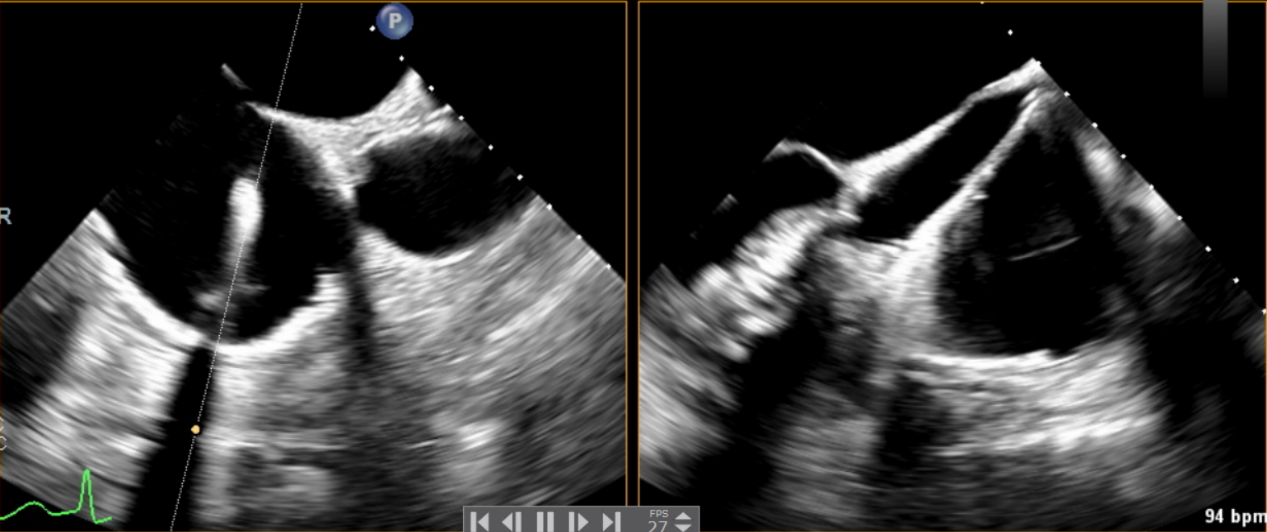

近日,美國(guó)紐約Montefiore醫(yī)學(xué)中心(Montrefiore Medical Center)的Azeem Latib教授團(tuán)隊(duì)成功應(yīng)用LuX-Valve Plus經(jīng)血管三尖瓣置換系統(tǒng)為兩位三尖瓣大量反流的患者完成三尖瓣置換手術(shù)。術(shù)后超聲顯示人工三尖瓣植入穩(wěn)定,瓣葉啟閉良好,僅殘余微量瓣周漏?;颊哂谑中g(shù)室即刻拔除氣管插管,血流動(dòng)力學(xué)改善顯著。此次手術(shù)是LuX-Valve Plus于紐約的首次臨床應(yīng)用,治療效果優(yōu)異。

術(shù)后超聲提示無(wú)瓣周漏

術(shù)后超聲提示僅殘余輕微瓣周漏